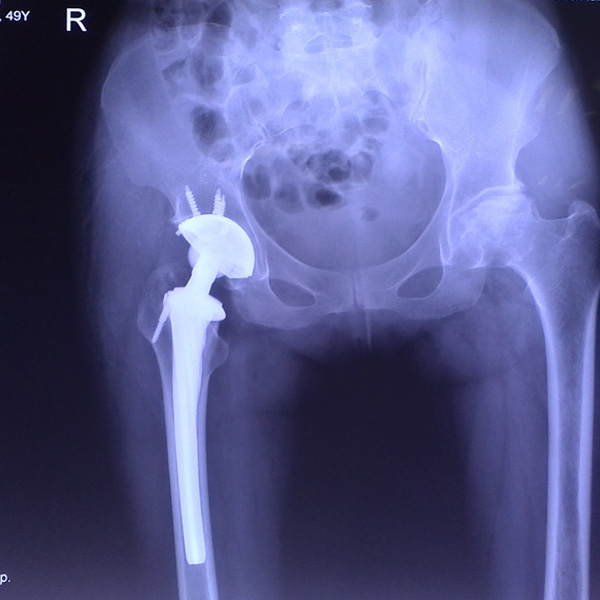

右側(cè)全髖關(guān)節(jié)置換

患者姜某某,女50歲,診斷為“股骨頭壞死”,右側(cè)髖關(guān)節(jié)疼痛到不能生活自理。經(jīng)平臺(tái)推薦到哈爾濱醫(yī)科大學(xué)附屬第二醫(yī)院骨關(guān)節(jié)科就診,患者想......